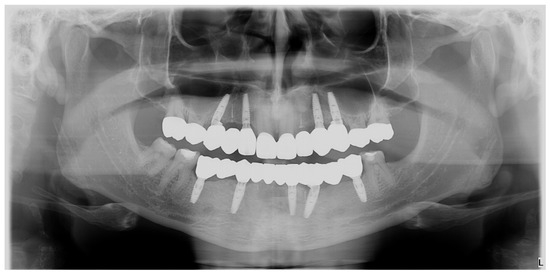

Figure 4.

OPG. Radiographic initial situation of the patient. The radiograph reveals the presence of 7 permanent teeth on the dental arches.

Radiographic examination did not reveal periapical alteration of the present teeth and excluded the diagnosis of dental impaction (Figure 4).

The radiological evaluation (Figure 21) of the final restorations showed good osseointegration of the implants with optimal bony peaks. Also, the submerged roots can be observed for the PET used to maintain the tissues in place.

Figure 21.

Control OPG: the final situation after the implant–prosthetic treatment.